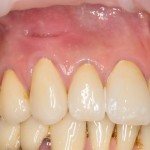

Исходная ситуация до начала лечения:

На клыком хорошо заметен рубец от проведенной две недели назад периостотомии. Зуб под коронкой.